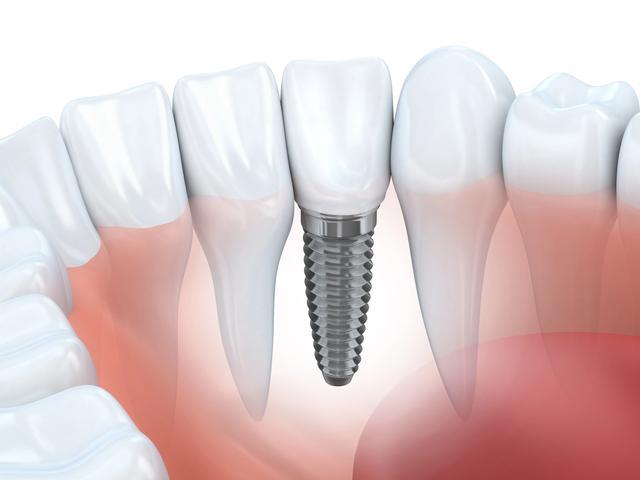

种植牙简单来说,就是将医用钛合金种植体通过手术植入牙槽骨内,替代天然牙根,再在上面安装牙冠,从而恢复牙齿的咀嚼和美观功能,规范操作下成功率可达95%以上。

因此被业界称为人类的第三副牙齿。但它本质上是一项有创外科手术,涉及骨结合、口腔微生物环境等多个复杂环节,其中哪一步最容易出现问题,引发风险呢?